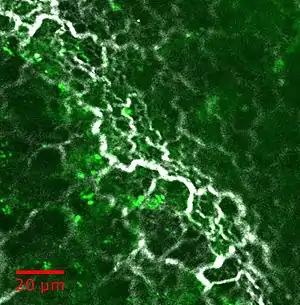

La microscopie SHG et ses extensions peuvent être utilisées pour étudier divers tissus: quelques exemples d'images sont rapportés dans la figure ci-dessous: le collagène à l'intérieur de la matrice extra-cellulaire reste la principale application. On le retrouve dans les tendons, la peau, les os, la cornée, les artères, le fascia, le cartilage, le ménisque, les disques intervertébraux...

La myosine peut également être imagée par SHG : dans le muscle squelettique, le muscle cardiaque.